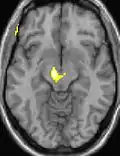

| La morphométrie voxel par voxel (VBM) montre les différences structurelles des zones du cerveau | ||

Les images par tomographie à émission de positron indiquent les régions du cerveau qui sont activées lors de la douleur, par rapport aux périodes sans douleur. Elles montrent les régions du cerveau qui sont toujours actives durant la douleur en jaune/orange (appelé "matrice-douleur"). La zone au centre (dans les trois vues) est spécifiquement activée uniquement pendant la crise. Les photos sur la ligne du bas (effectuées par VBM) montrent les différences structurelles entre les patients souffrant d'AVF et des personnes saines : seulement une partie de l'hypothalamus est différente[50],[51].